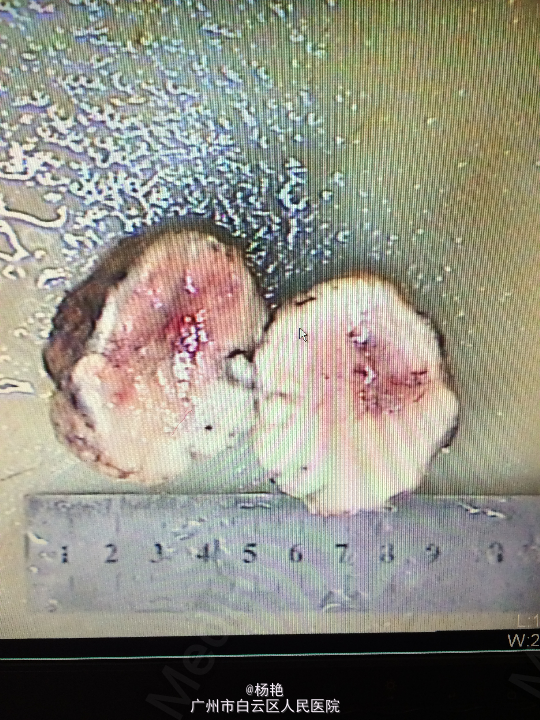

诊断:左额叶脑膜瘤 处理:在静脉全麻下行左侧额底脑膜瘤切除术,术后病理提示:脑膜瘤